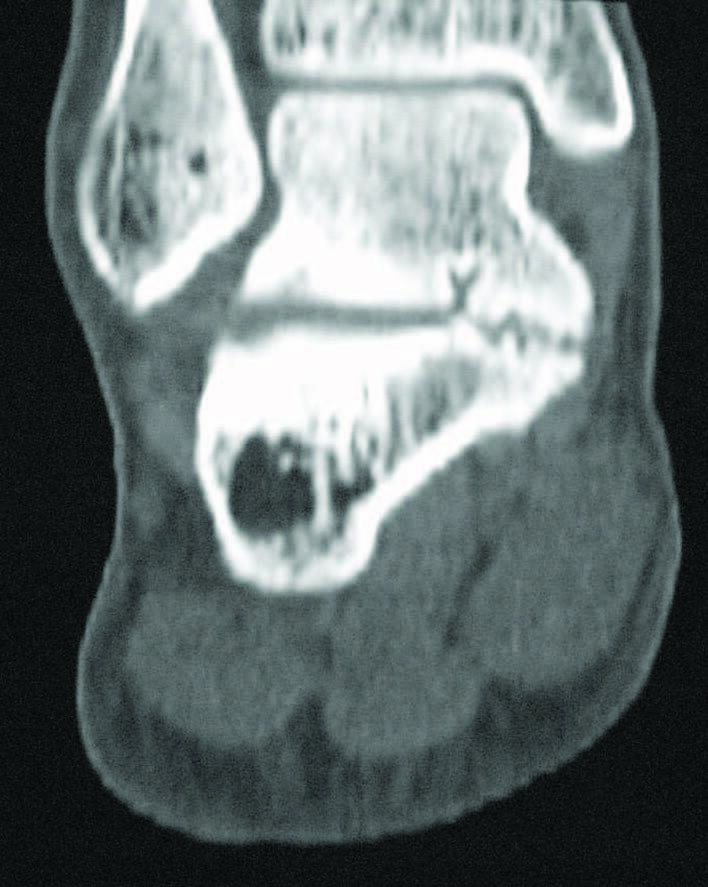

A tarsal coalition exists when there is a congenital, complete or incomplete union between two or more tarsal bones causing restricted motion or absence of motion. Tarsal coalitions remain challenging for the foot and ankle physician and surgeon. Their clinical hallmarks are primarily pain, rigid pes valgus and/or rigid pes planus deformity, and often tonic peroneal muscle spasm. Although the diagnosis of a tarsal coalition is often readily apparent upon clinical examination, diagnostic imaging is confirmatory and often aids in planning any necessary surgical intervention. Sequentially, the author always obtains radiographs of the involved foot first followed as necessary by advanced imaging with either computerized tomography (CT) or magnetic resonance imaging (MRI) scans, or in some instances of incomplete tarsal coalition, both CT and MRI.1

Recently, the literature presents arguments for the inclusion of the size and type of talocalcaneal coalition, and the degree of heel valgus as factors to consider when deciding between joint resection and joint fusion.3-11 Some hypothesize that the size of a talocalcaneal coalition inversely correlates with the success rate of resection, and some researchers used preoperative advanced imaging studies, particularly CT, to investigate.3,4 Arbitrarily, based only on their personal experience, these investigators concluded that talocalcaneal coalitions involving greater than 50 percent of the talocalcaneal joint are less amenable to surgical resection.3,4 More recently though, several authors challenged this subjective assumption and instead determined that no definitive talocalcaneal coalition size precludes an attempt at resection in every patient.5-7

Additionally, different described shapes and morphologies of talocalcaneal coalitions may be a factor to consider when debating arthroplasty or arthrodesis. In 2010, Rozansky and colleagues used thin-cut 2D and 3D CT scans to divide talocalcaneal coalitions into five different types based on their cartilaginous or bony nature, location and facet joint orientation.8 In 2016, Bixby and associates used CT scans to assess 97 patients with a total of 138 talocalcaneal coalitions.9 They found that 97 (70 percent) of the coalitions involved the middle facet, 39 (28 percent) the posteromedial aspect of the joint and two (1.4 percent) involved the posterior facet.9 They described the posteromedial talocalcaneal coalition as being associated with an intact, but shorter middle facet with a long sustentaculum tali.9

Can CT Scans Play A Role Intraoperatively?

Recently, CT scans have been used to assist not only in preoperative planning but also intraoperatively. In 2014, de Wouters and colleagues preoperatively created patient-specific instrument guides by 3D CT scan modeling of the coalition and then used the guides to resect a series of seven talocalcaneal coalitions.17 The guides were made-to-measure and designed to fit the coalition, enabling potentially more precise resection. They found that the guides resulted in easier and more predictable resection of the talocalcaneal coalitions in their series.17 Since this original description, other surgeons also advocated the use of customized 3D-printed surgical guides based on 3D CT reconstructions for talocalcaneal coalition resection.18

Kemppainen and associates retrospectively looked at 14 feet where intraoperative CT assessed talocalcaneal resection.19They found that intraoperative CT scans altered their operative technique in three (21 percent) of the 14 feet. On blinded review, use of intraoperative CT resulted in an “excellent” resection of the coalition in eight (57 percent) of the 14 feet compared to three (25 percent) of the 12 feet in their control group that underwent treatment without intraoperative CT scan assistance.19

In 2017, Aibinder and colleagues introduced an interesting technique of intraoperative CT-guided navigation for resection of a talocalcaneal coalition.20 Their technique required placement of a reference frame and performance of two intraoperative CT scans. The first scan delineated the coalition, and the second scan took place after a navigated burr resected the coalition. The authors hypothesized that their technique allowed for efficient, more thorough, and more controlled resection of the coalition along with decreased risk of incomplete resection. The noted disadvantages of this technique are radiation exposure and increased cost of using intraoperative CT scans.20

In 2018, Stokman and team also described the use of intraoperative CT navigation to assist in immediate localization and guided resection of talocalcaneal coalitions.21 They used a high-speed burr to resect the coalition that, unlike the technique used by Aibinder and colleagues, was not registered to the navigation system.21 Although these preoperative and intraoperative techniques utilizing 3D-CT scanning and 3D-modeling/printing technologies are not yet in widespread use, they clearly merit further investigation and comparison of clinical outcomes achieved with these methods to those achieved with more traditional surgical approaches.